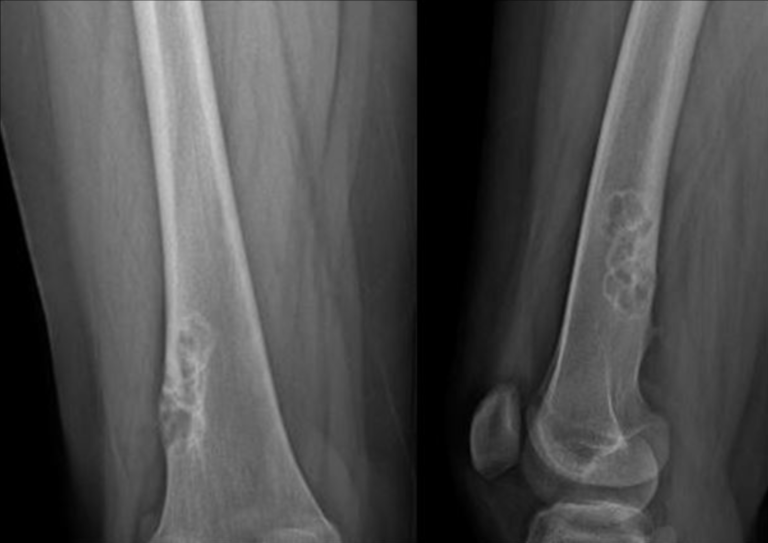

Direkt Grafi (Röntgen)

o Litik ve düzensiz multilokule bir görüntü ile kaşımıza çıkar. Etrafı düzgün ve sklerotik sınırlarla çevrilidir.

o Lezyonun uzun aksı genellikle kemiğe paralel seyreder.

o Sıklıkla metafizyel ve ekzantrik yerleşimlidir ve korteksi içerir.

o Bazen genişlemiş ve çevresi keskin sınırlarla çizili gibi karşımıza çıkabilir.

o Sıklıkla reaktif trabekülasyonlar içerir.

Distal femurda NOF’u olan, uzun süre takip ettiğim hastanın direkt grafi görüntüsü.